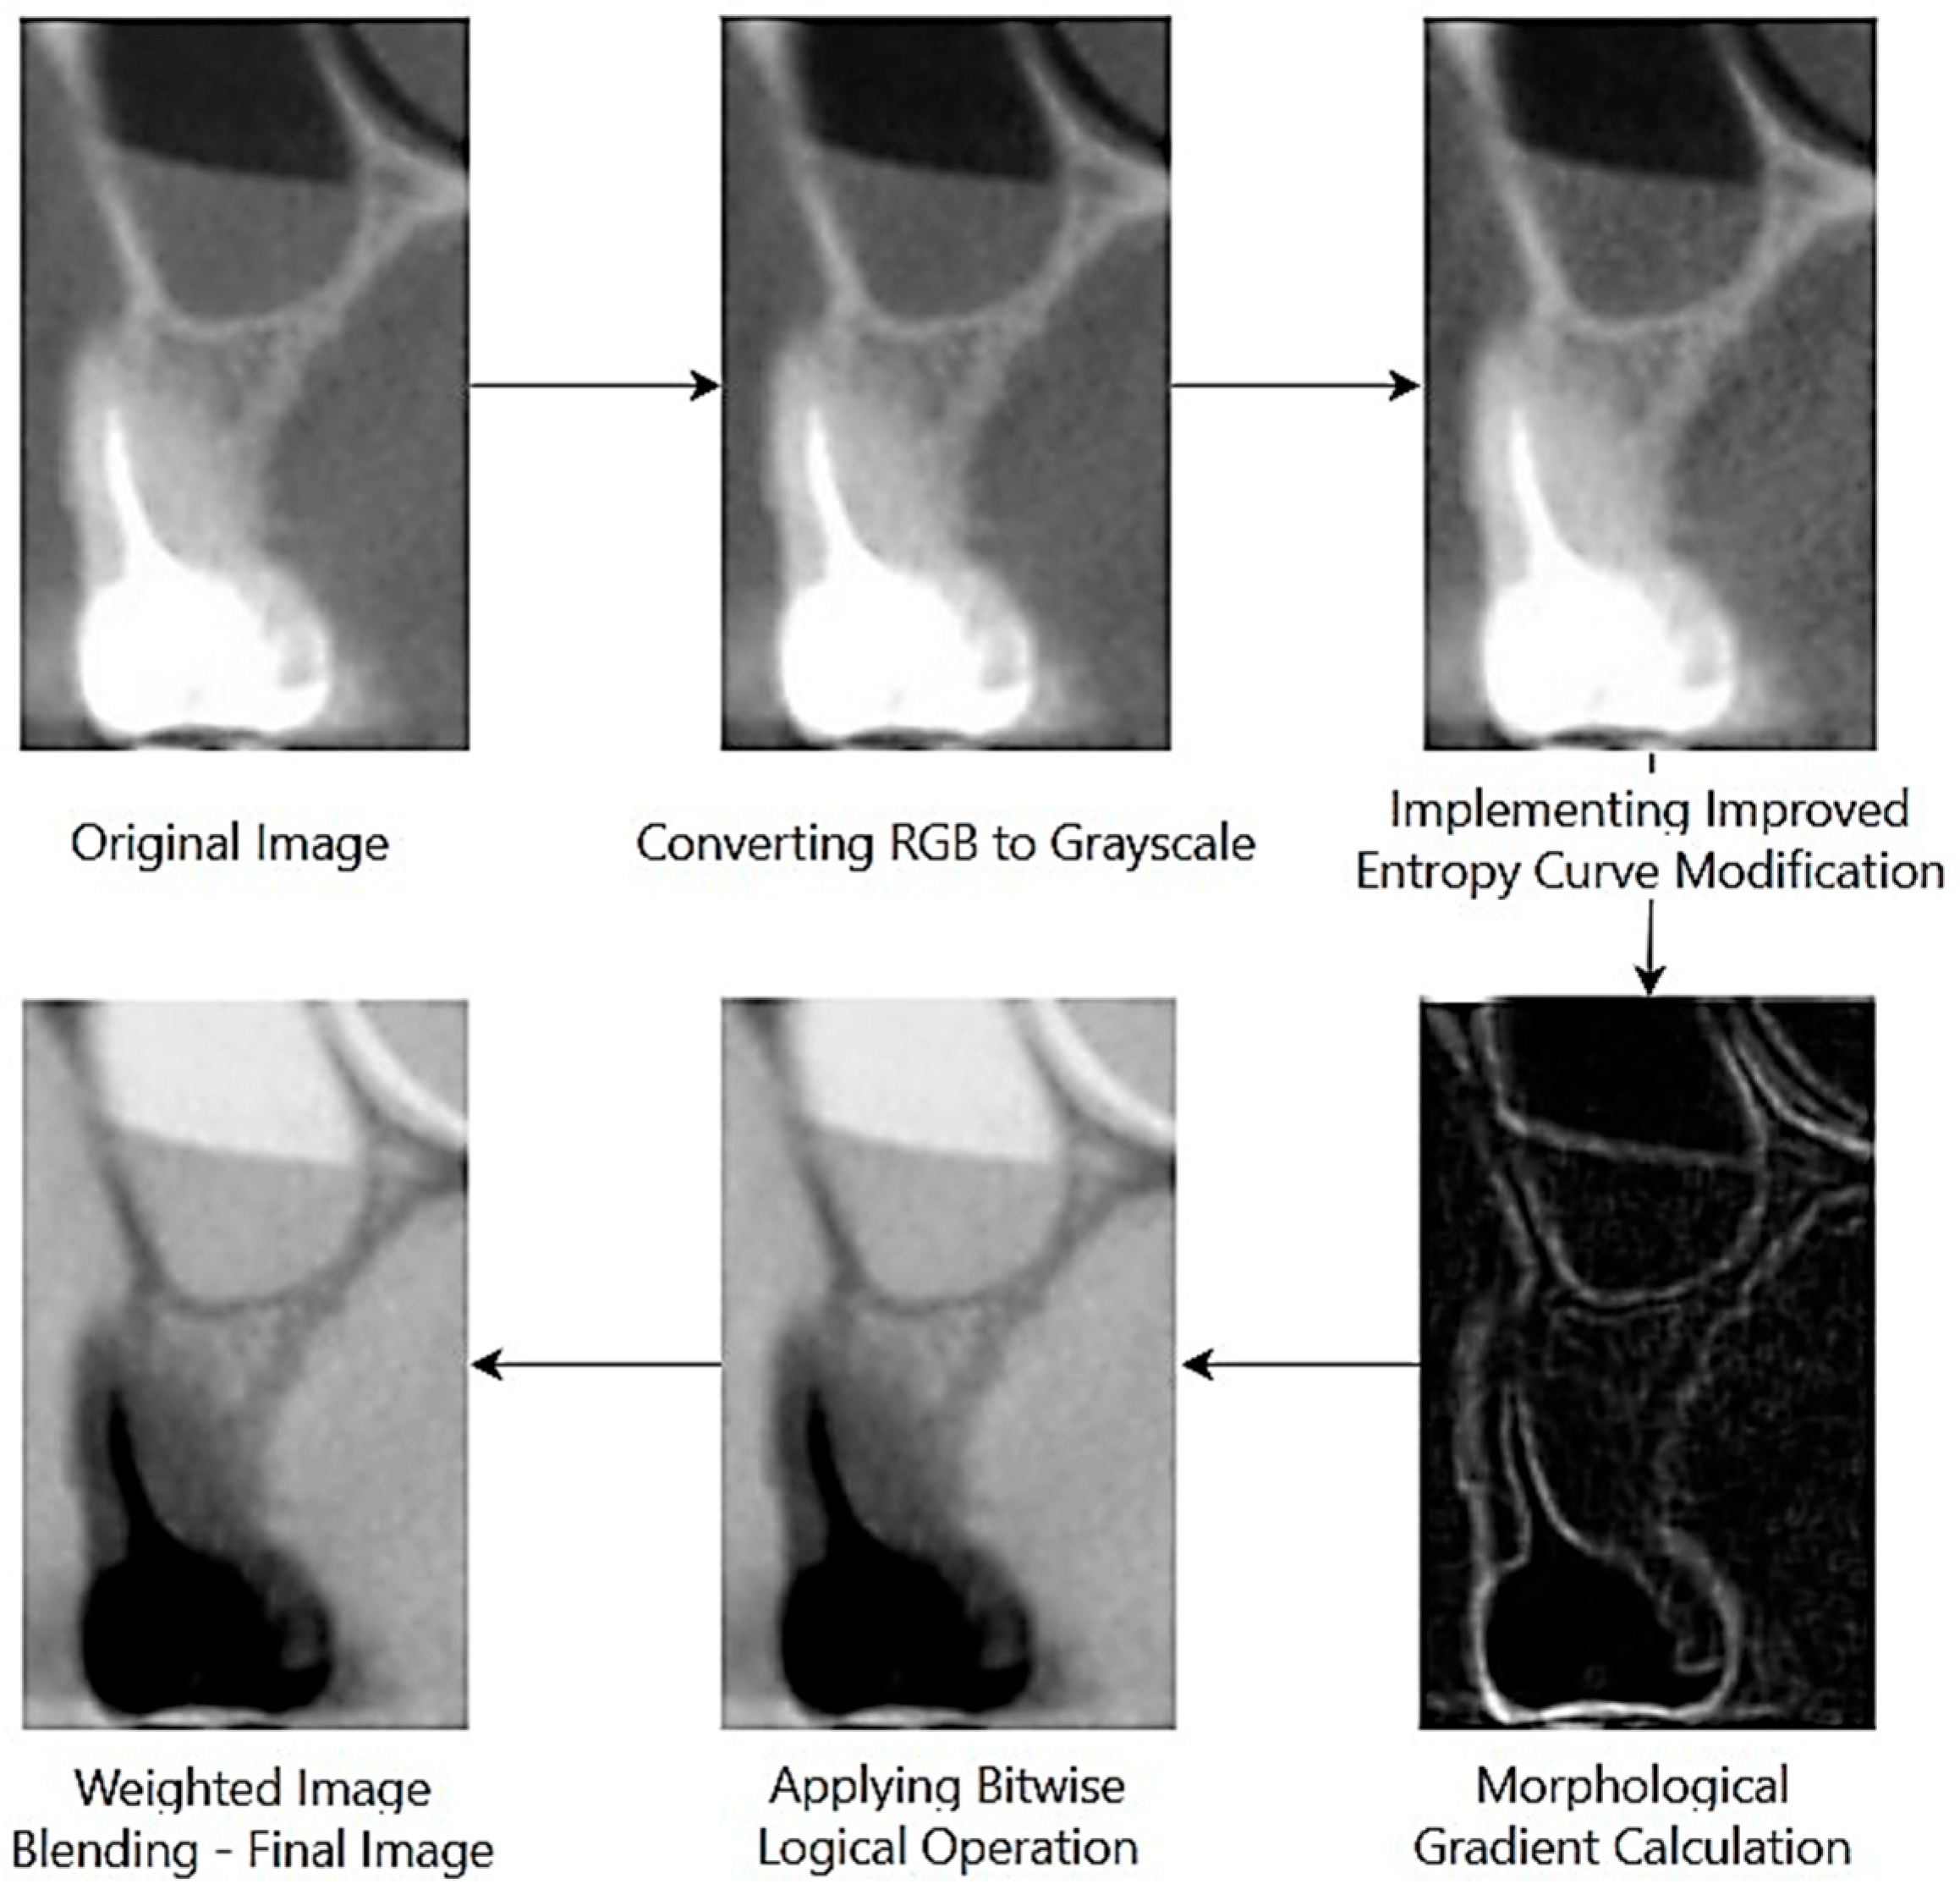

The flow diagram of the 3 basic steps of proposed image processing approach 1 for images with and without lesions is given in Figure 2 and Figure 3.

The enhanced images shown in Figure 2 and Figure 3 were converted into data where sensitive points and boundaries were highlighted.

The image processing approach successfully localized pixel values ranging from 0 to 255. This offers the potential for a powerful feature set for the classification of images with and without lesions.

Figure 3. Stages of implementation of proposed image processing approach on a withoutlesion image [30].